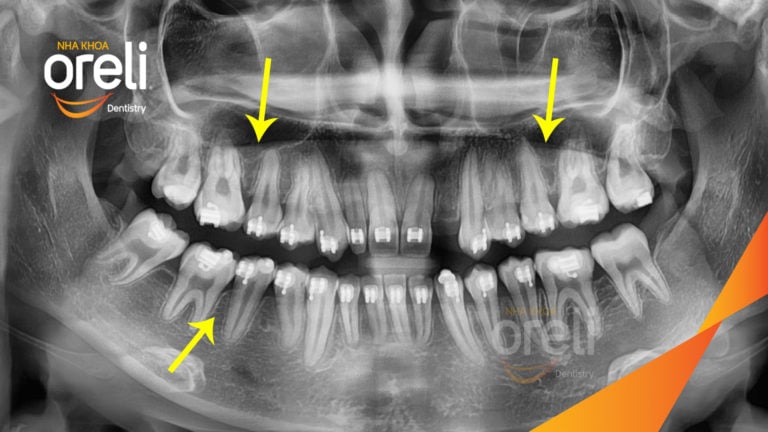

Ca niềng răng sai khớp cắn hạng 3 móm chen chúc kèm di gần răng số 7 8 thay thế răng 6 ở Oreli Niềng răngChen chúcDi gần răng 7 8Móm Xem thêm